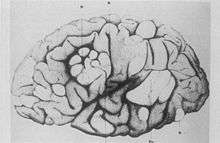

- French neurologist Désiré-Magloire Bourneville had a chance encounter with the disease that would bear his name. He was working as an unofficial assistant to Jean Martin Charcot at La Salpêtrière.[10] While substituting for his teacher, Louis J.F. Delasiauve,[12] he attended to Marie, a 15-year-old girl with psychomotor retardation, epilepsy and a "confluent vascular-papulous eruption of the nose, the cheeks and forehead". She had a history of seizures since infancy and was taken to the children's hospital aged three and declared a hopeless case. She had learning difficulties and could neither walk nor talk. While under Bourneville's care, Marie had an ever increasing number of seizures, which came in clusters. She was treated with quinquina, bromide of camphor, amyl nitrite, and the application of leeches behind the ears. On 7 May 1879 Marie died in her hospital bed. The post-mortem examination disclosed hard, dense tubers in the cerebral convolutions, which Bourneville named Sclérose tubéreuse des circonvolutions cérébrales. He concluded they were the source (focus) of her seizures. In addition, whitish hard masses, one "the size of a walnut", were found in both kidneys.[13]